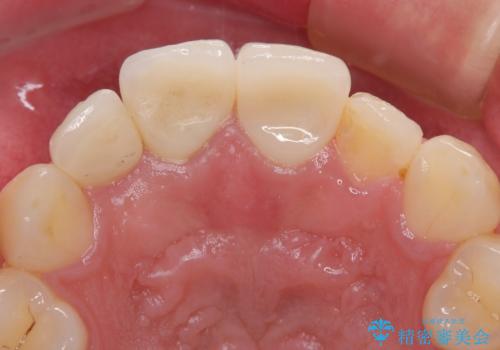

歯が欠けるほどの強い衝撃を受けると、歯根が溶けてしまう外部吸収という現象を起こすことがあるため、補綴治療後しばらく様子を見ておりましたが、何と三度自転車事故に遭いかけてしまいました。